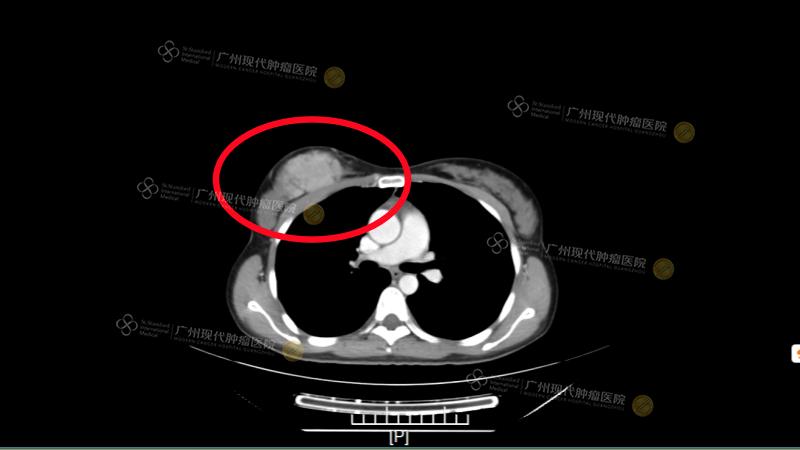

(2018年8月28日,罗其琂初次入院CT)

2018年8月28日,罗其琂正式入院。经过详细的入院检查和多学科联合会诊后,医院乳癌专科负责人戴文燕主任为她制定了个性化的整合微创治疗方案:介入动脉灌注化疗结合栓塞+冷冻治疗。

治疗结果确实令人欣喜。经过系统治疗,第四次疗效评估显示,罗其琂的右乳肿瘤缩小了50%~60%,达到部分缓解(PR)状态;2019年1月最后一次复查时,经影像学评估,罗其琂的原发肿瘤灶和腋窝淋巴结转移灶情况已经达到临床完全缓解(CR)的状态。

(2018年初次入院VS 2019年1月最后复查:大部分癌细胞已失去活性)